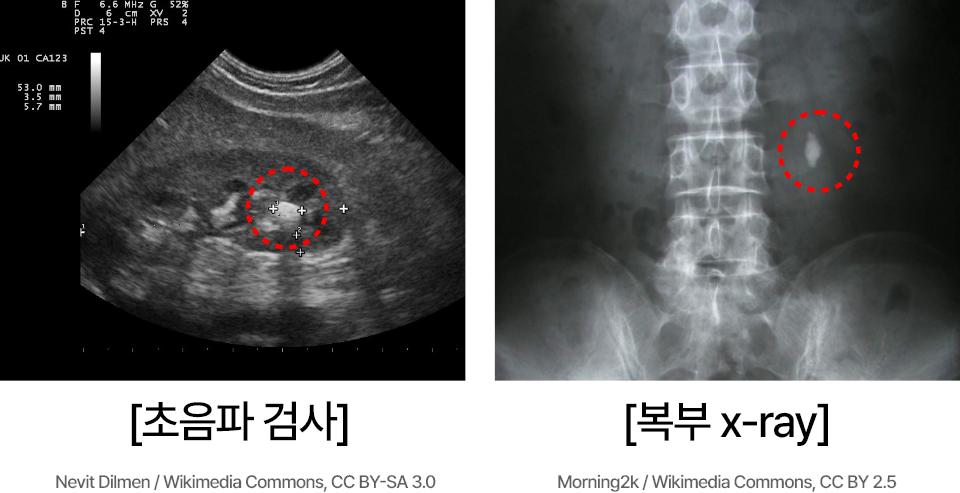

요로결석은 신장, 요관, 요도, 방광 등 요로 기관에 단단한 돌(결석)이 생겨

통증을 유발하는 대표적인 비뇨기 질환입니다.